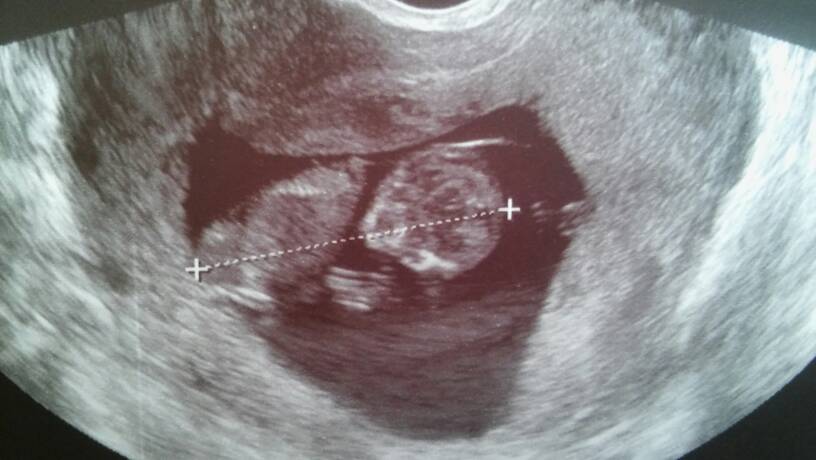

Zdjęcia z dzisiejszej wizyty.

20170316_141610.jpg

20170316_141600.jpg